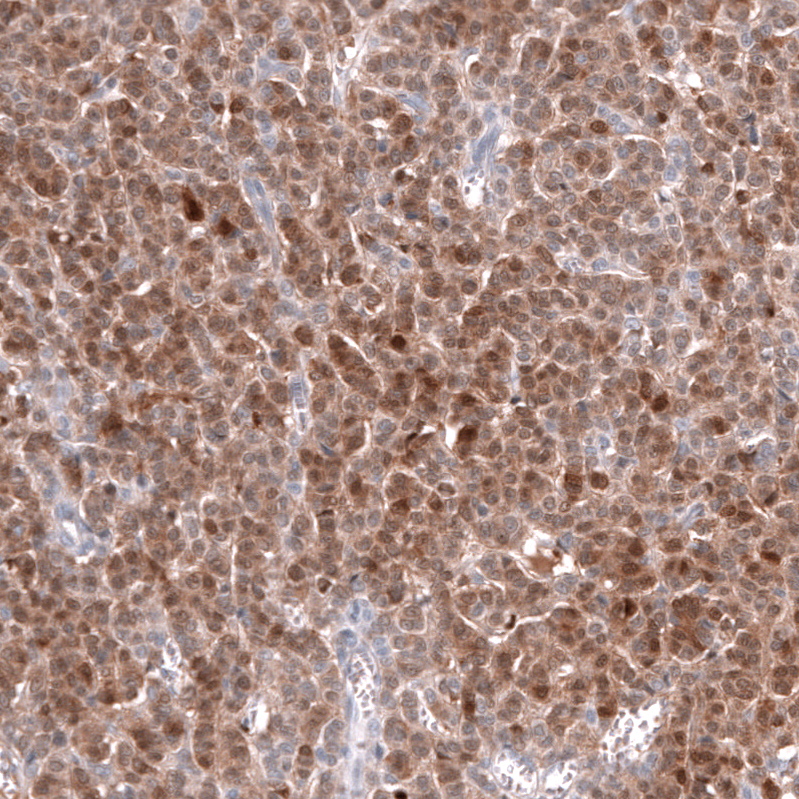

Immunohistochemistry analysis in human cerebral cortex and liver tissues using AMAb91814 antibody. Corresponding CALB2 RNA-seq data are presented for the same tissues.